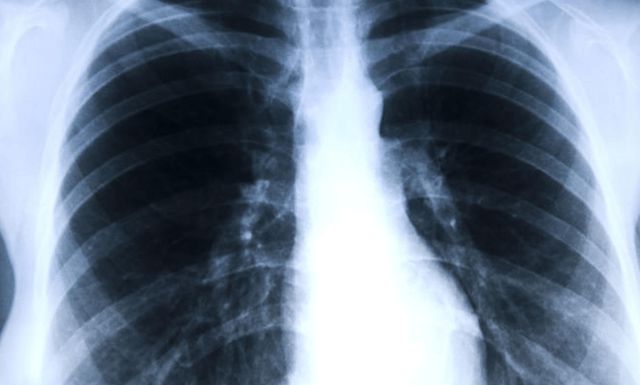

肺结节是肺病中发病率较高的一种,在发病初期,身体表现往往不够明显,因而易被人们忽视,等到病情严重时,才引起重视,此时再想彻底治愈,其希望往往已比较渺茫。吸烟的人大部分都有肺结节,这是因为烟草中的有害物质长期刺激肺部,使肺部产生炎症,引起结节。

有人发现肺结节后,经进一步检查后提示为良性,认为可松一口气。但是肺结节也在不断变化,只要直径大于5毫米,就属于危险较大的结节,需要每3-6个月复查一次,密切关注肺结节的变化,以便及时手术治疗。

据统计,肺结节的恶变率约为20%。肺结节的出现与吸烟和被动吸烟密切相关,一旦发现肺结节不戒烟,肺结节的恶变率将是其他人的20倍,可见吸烟确实是肺结节的高风险因素。这是因为香烟中含有的尼古丁等有害气体被吸入肺部后,会对肺部造成一定的损伤,导致肺结节、肺气肿或慢性支气管炎的风险。